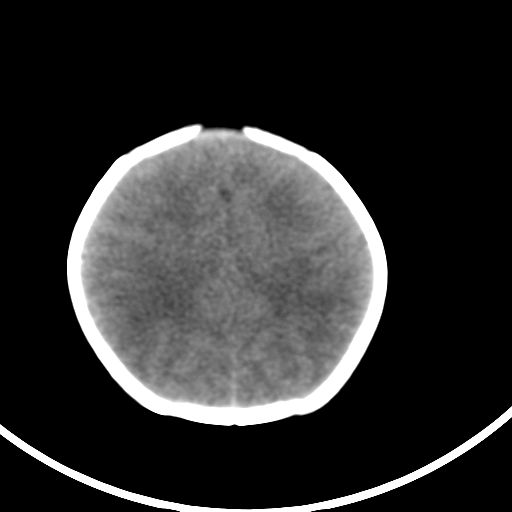

新生儿3天,超过预产期5天剖宫产,有缺氧病史,具体评分不详,现反应差,肌张力低,前囟平,原始反射存在,无苦闹等。

正常颅脑表现。

kaolv小脑幕,后纵裂区蛛网膜下腔出血;轻度脑肿胀

矢状窦旁征——支持蛛网膜下腔出血